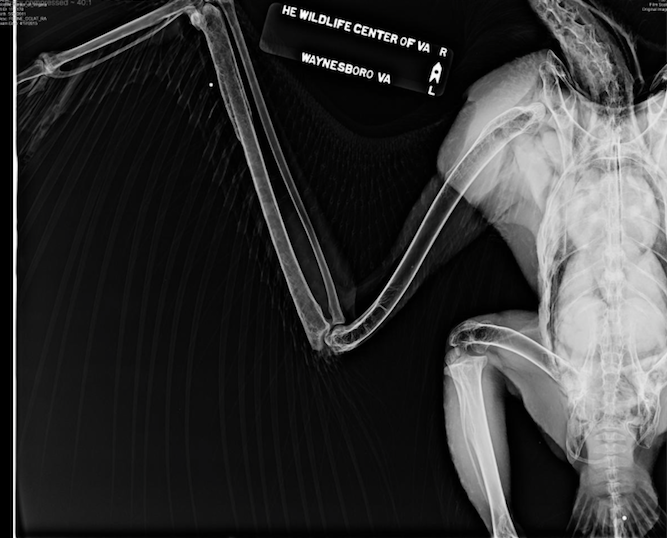

The injured bird was taken the center the same day. That’s when Dr. Meghan Feeney found that a large laceration on the left wing. Muscle and bone was exposed and he bird was bleeding. Radiographs showed the wing bone fractured into multiple fragments, a fracture of the left ulna and a collapsed elbow joint.

The veterinarians also spotted two pellets on the X-rays. One was above the tail, and the other, near the right ulna.

“There were also changes to the right ulna, indicated that the eagle sustained previous trauma that had healed. It’s likely that the bird’s ulna was fractured from a gunshot wound,” the center said.